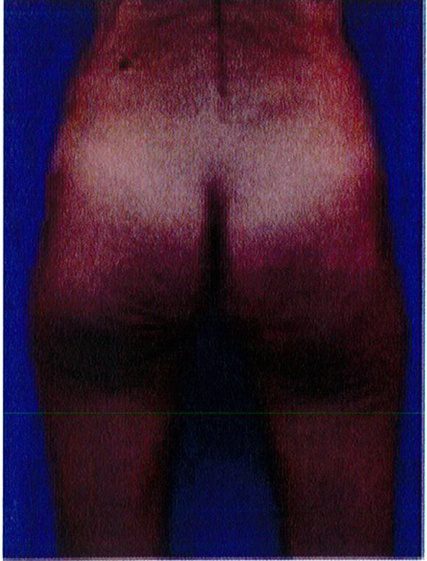

Hình. 20. (A) Hình anh trước và (B) và sau phẫu thuật làm đầy mông của bệnh nhân có vùng mông tương đối đầy đặn. Bệnh nhân được đặt khối implant dưới cân thể tích 330 mL ở hai bên.

THỜI GIAN HỒI PHỤC SAU MỔ

Bệnh nhân 30 tuổi mong muốn cải thiện hình dáng vòng ba, mặc dù vòng mông đã tương đối đây đặn. Bác sĩ sau khi đánh giá đã đưa ra quyết định hút mỡ eo và làm đầy mông bằng implant. Hai khối implant microtextured (vi nhám) thể tích 330 mL được đặt cân đối ở hai bên. Bệnh nhân sau phẫu thuật xuất hiện bục một phần vết mổ (dài khoảng 2cm) ở hai bên nhưng không sâu và đã điều trị kịp thời bằng dung dịch sát khuẩn, kháng sinh tại chỗ và toàn thân. Vết mổ liền lại tốt (Hình 20).